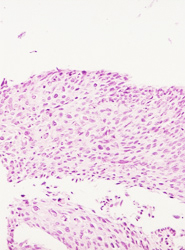

El resultado de una valoración colposcópica de paciente con lesión displásica siempre será confirmado por el estudio histopatológico que realiza el médico anatomopatólogo (estudio de la biopsia tomada en la colposcopía) . A continuación presentamos imágenes histológicas con sus diagnósticos.

• Lesión de alto grado, con anisocitosis y anisocariosis severas, hipercromasia nuclear, con algunas células apoptoticas.

• Atipias nucleares severas en una neoplasia intraepitelial cervical de alto grado, llama la atención las células apoptoticas.